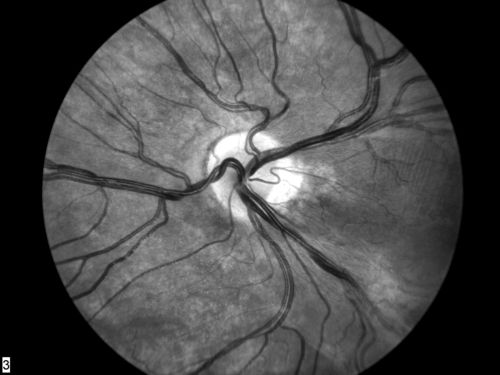

FEVR in OS of a 14 yr old girl

FEVR

Familial Exudative Vitreoretinopathy

Marissa Scherf

Device with which Image was Captured::

Zeiss FF4